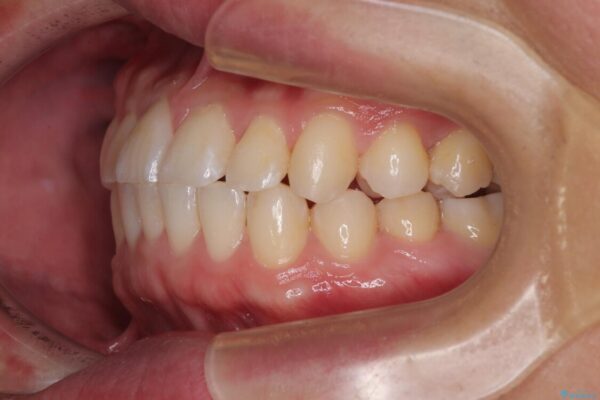

治療後

• 前歯のガタガタ・奥歯のかみ合わせ(シザーズバイト)を改善|1年半で完了したメタルブラケット矯正 治療後画像

**前歯のデコボコ(叢生)**が整い、歯列全体が美しく改善

シザーズバイトの奥歯も正常なかみ合わせに改善

捻転歯も回転が修正され、全体的に清掃性・咀嚼効率が向上